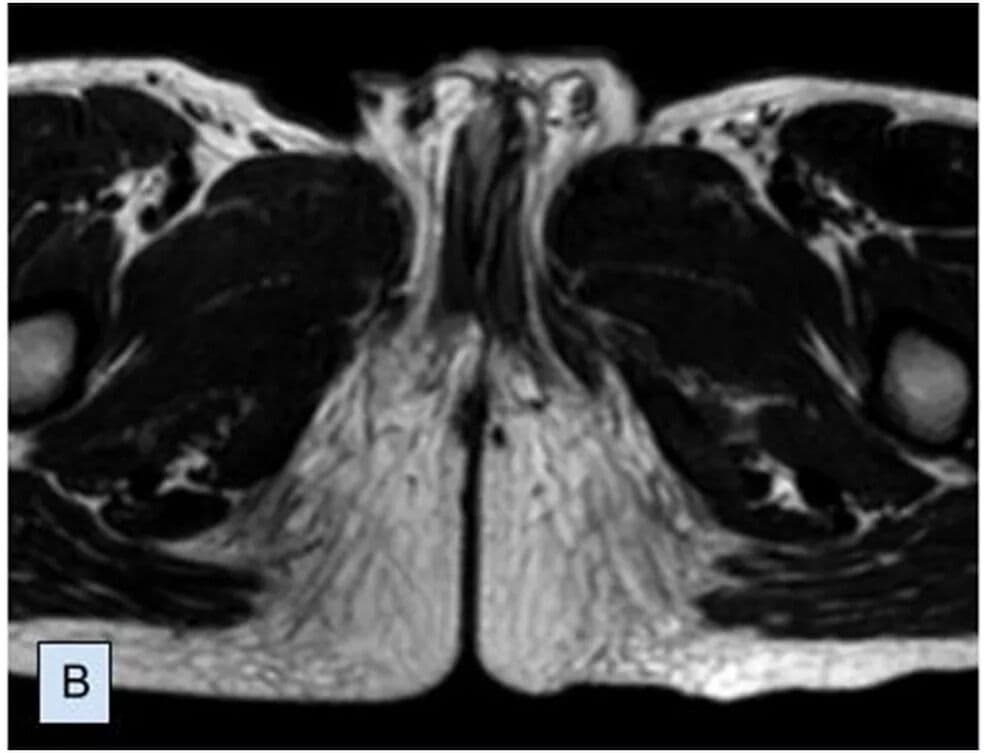

Em caso raríssimo, menino nasce com dois pênis e passa por cirurgia